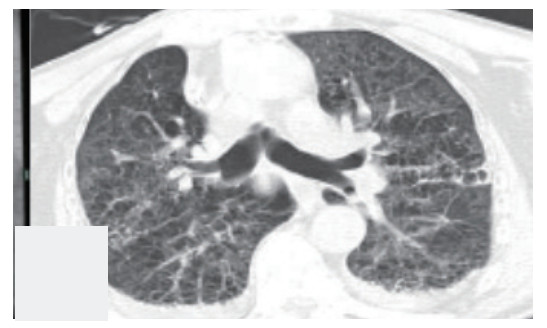

气管镜检查于当日10:20结束,在10:30患者在复苏醒过程中突发氧饱和度下降至60%,立即予纤支镜复检发现左下叶背段活动性出血,立即给予气管插管,局部去甲肾上腺素止血,垂体后叶素6 mg静注,甲强龙针80 mg静注,呋塞米20 mg静注等对症处理后,气管镜再次给予负压吸引,1 min后出血停止,患者氧饱和度恢复至82%。气管镜下未见明显出血。立即行胸部CT检查示两肺弥漫渗出影(见图 4),给予患者气管插管后转入ICU治疗。

| 两肺弥漫渗出,小叶间隔增厚 图 4 病例2气管镜术后(2020年5月8日)当天胸部CT |